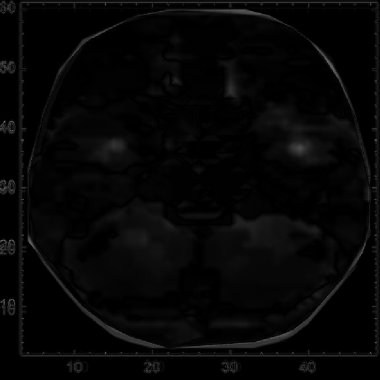

From this list of 3D plots, we can take the image of the corresponding 2D fMRI density cross-section plot:

In[]:=

imagesOfScans=Image/@ListDensityPlot/@combinedVoxelData

Out[]=

Iterating across these 9 density plots, we create a mean image of the activation for the participants in the study:

meanScan=Image[Mean[Rasterize/@Map[ImageResize[#,{256,256}]&,imagesOfScans]]];​​ImageResize[meanScan,550]

To simplify image comparison, we convert the previous images for each participant and the mean to greyscale colors:

grayImagesOfScans=ColorConvert[#,"Grayscale"]&/@imagesOfScans​​grayMeanScan=ColorConvert[meanScan,"Grayscale"];​​ImageResize[grayMeanScan,550]